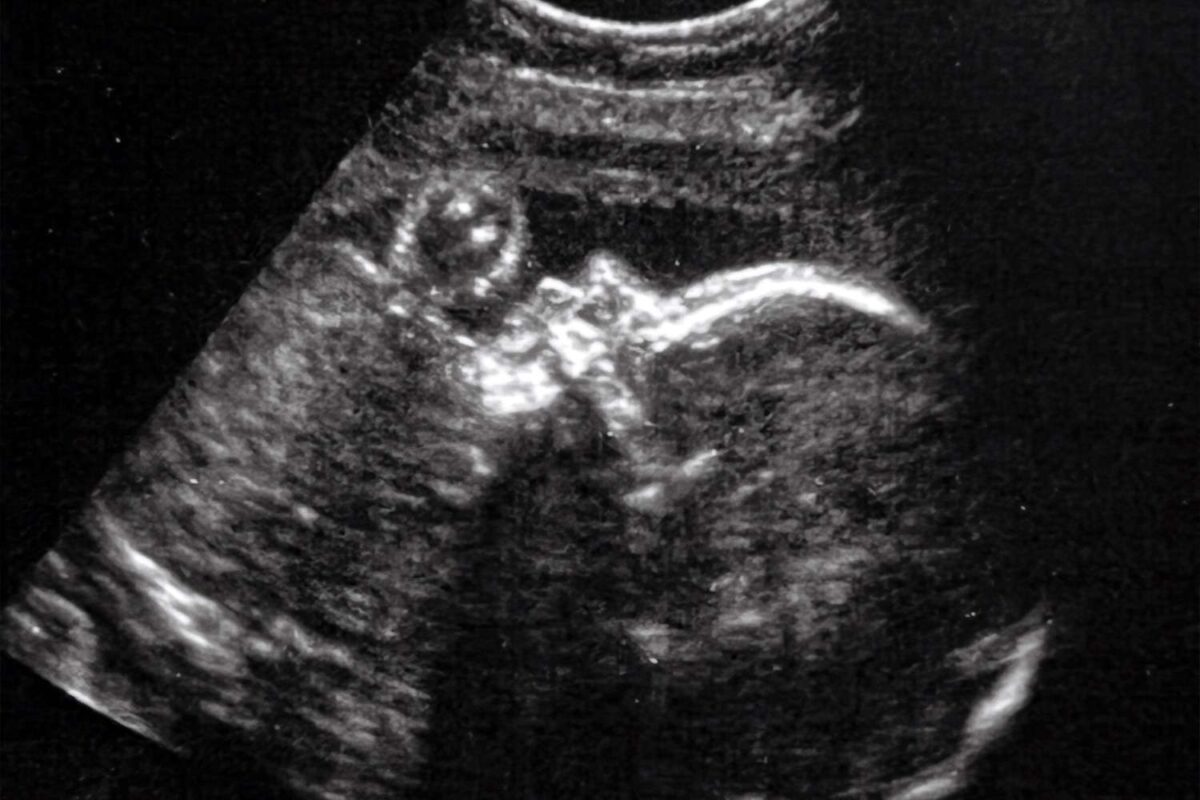

Αλλά όταν η Kenyatta πήγε για υπερηχογράφημα στις 30 εβδομάδες της εγκυμοσύνης της, ήρθε αντιμέτωπη με κάτι διαφορετικό. Θυμάται τον γιατρό της να την κάθεται και να λέει ότι ανησυχεί.

«Μοιράστηκε μαζί μου ότι κάτι δεν πήγαινε καλά όσον αφορά τον εγκέφαλο του μωρού και επίσης η καρδιά της είχε διευρυνθεί», είπε η Kenyatta.

Μετά από περισσότερη έρευνα, υπήρξε διάγνωση: VOGM.